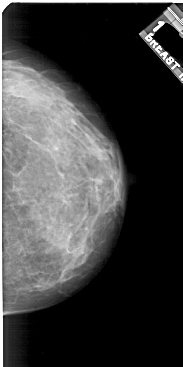

A_1921_1.LEFT_MLO

LEFT_MLO LINES 5371 PIXELS_PER_LINE 3076 BITS_PER_PIXEL 12 RESOLUTION 43.5 OVERLAY